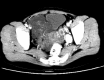

Intravenous leiomyomatosis (IVL), showing unusual growth patterns of uterine leiomyoma, is a rare neoplasm characterized by intravascular proliferation of a histologically benign-looking smooth muscle cell tumor mass, but not invading the tissue. To date, less than 300 cases have been reported and fewer than 100 cases with cardiac involvement. Imaging characteristics of IVL are still not clear so it is usually misdiagnosed before surgery. A 36-year-old woman, who had undergone hysterectomy due to hysteromyoma, presented with shortness of breath after activities. Imaging showed IVL with mass involvement of the left ovarian vein, left renal vein, left external and common iliac vein, as well as within the inferior vena cava (IVC), extending into the right atrium. The operation demonstrated that the mass had no stalk and had well-demarcated borders with the wall of the right atrium and IVC. The patient underwent a one-stage combined multidisciplinary thoraco-abdominal operation under general anesthetic. Subsequently, the pathology report confirmed IVL. IVL should be considered in a female patient presenting with an extensive mass in the right side of the heart. Imaging technology, such as echocardiogram, contrast-enhanced computed tomography and magnetic resonance imaging, can provide important information to reveal the mass, the range and path of the lesion, and relates to the surgical plan decision. Consequently, perfect and exact image examination is very necessary pre-operation.